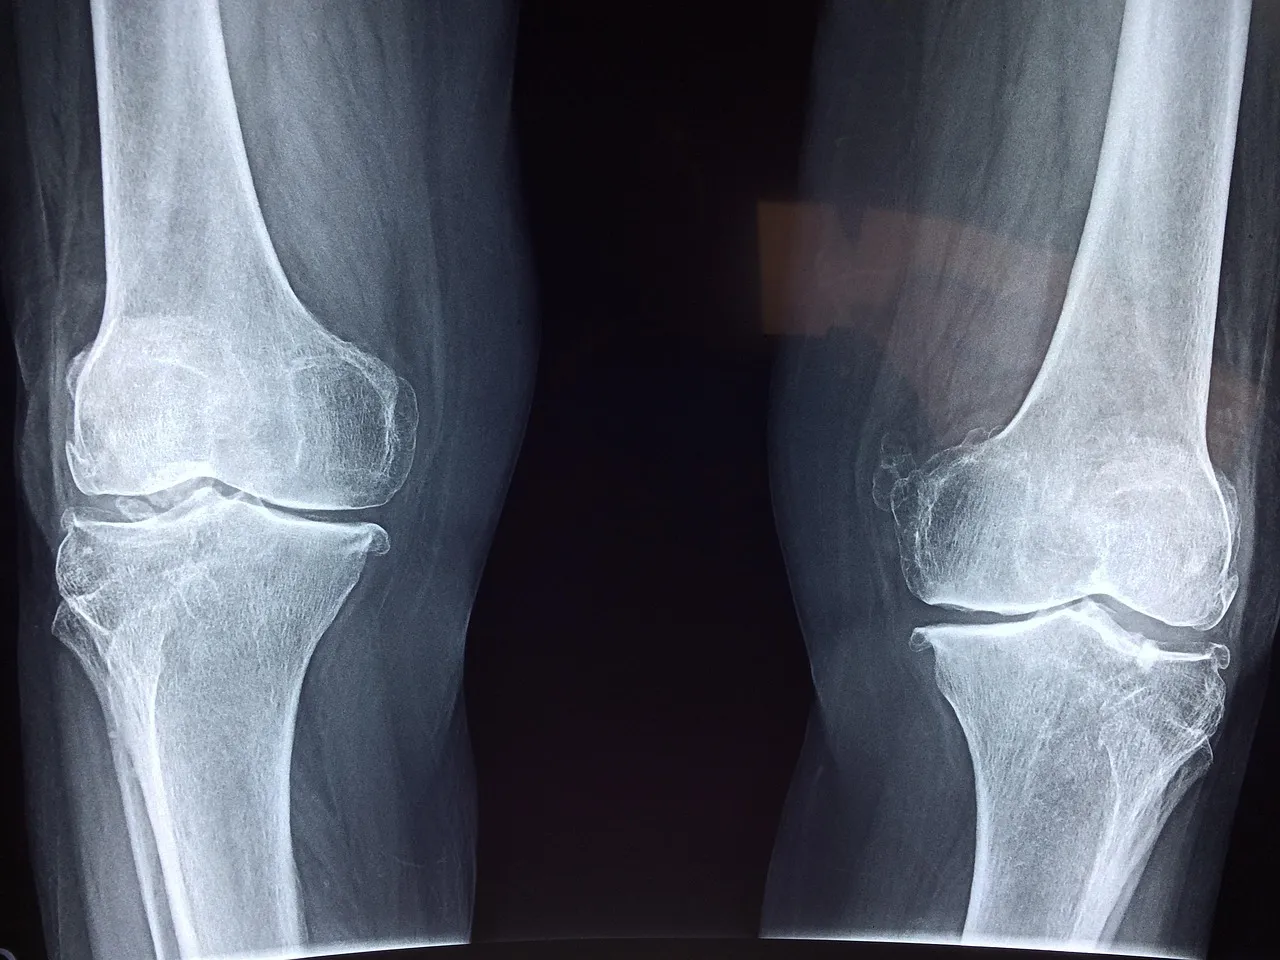

보스웰리아 효능 ① 관절염 개선 및 염증 완화

보스웰리아 효능 중 가장 대표적인 건 단연 관절 통증 완화입니다.

보스웰리아에는 ‘보스웰릭산(Boswellic Acid)’이라는 강력한 항염 성분이 들어 있는데,

이 성분이 관절 내 염증을 유발하는 효소(5-LOX)의 작용을 억제해줍니다.

보스웰리아 효능 ② 관절 연골 보호

보스웰리아는 단순히 통증만 줄이는 게 아니라,

관절을 구성하는 연골 손상을 예방해주는 역할도 합니다.

한 연구에 따르면, 보스웰리아 추출물을 8주 이상 꾸준히 섭취한 사람들의 연골 파괴 지표가 개선되었다고 합니다.